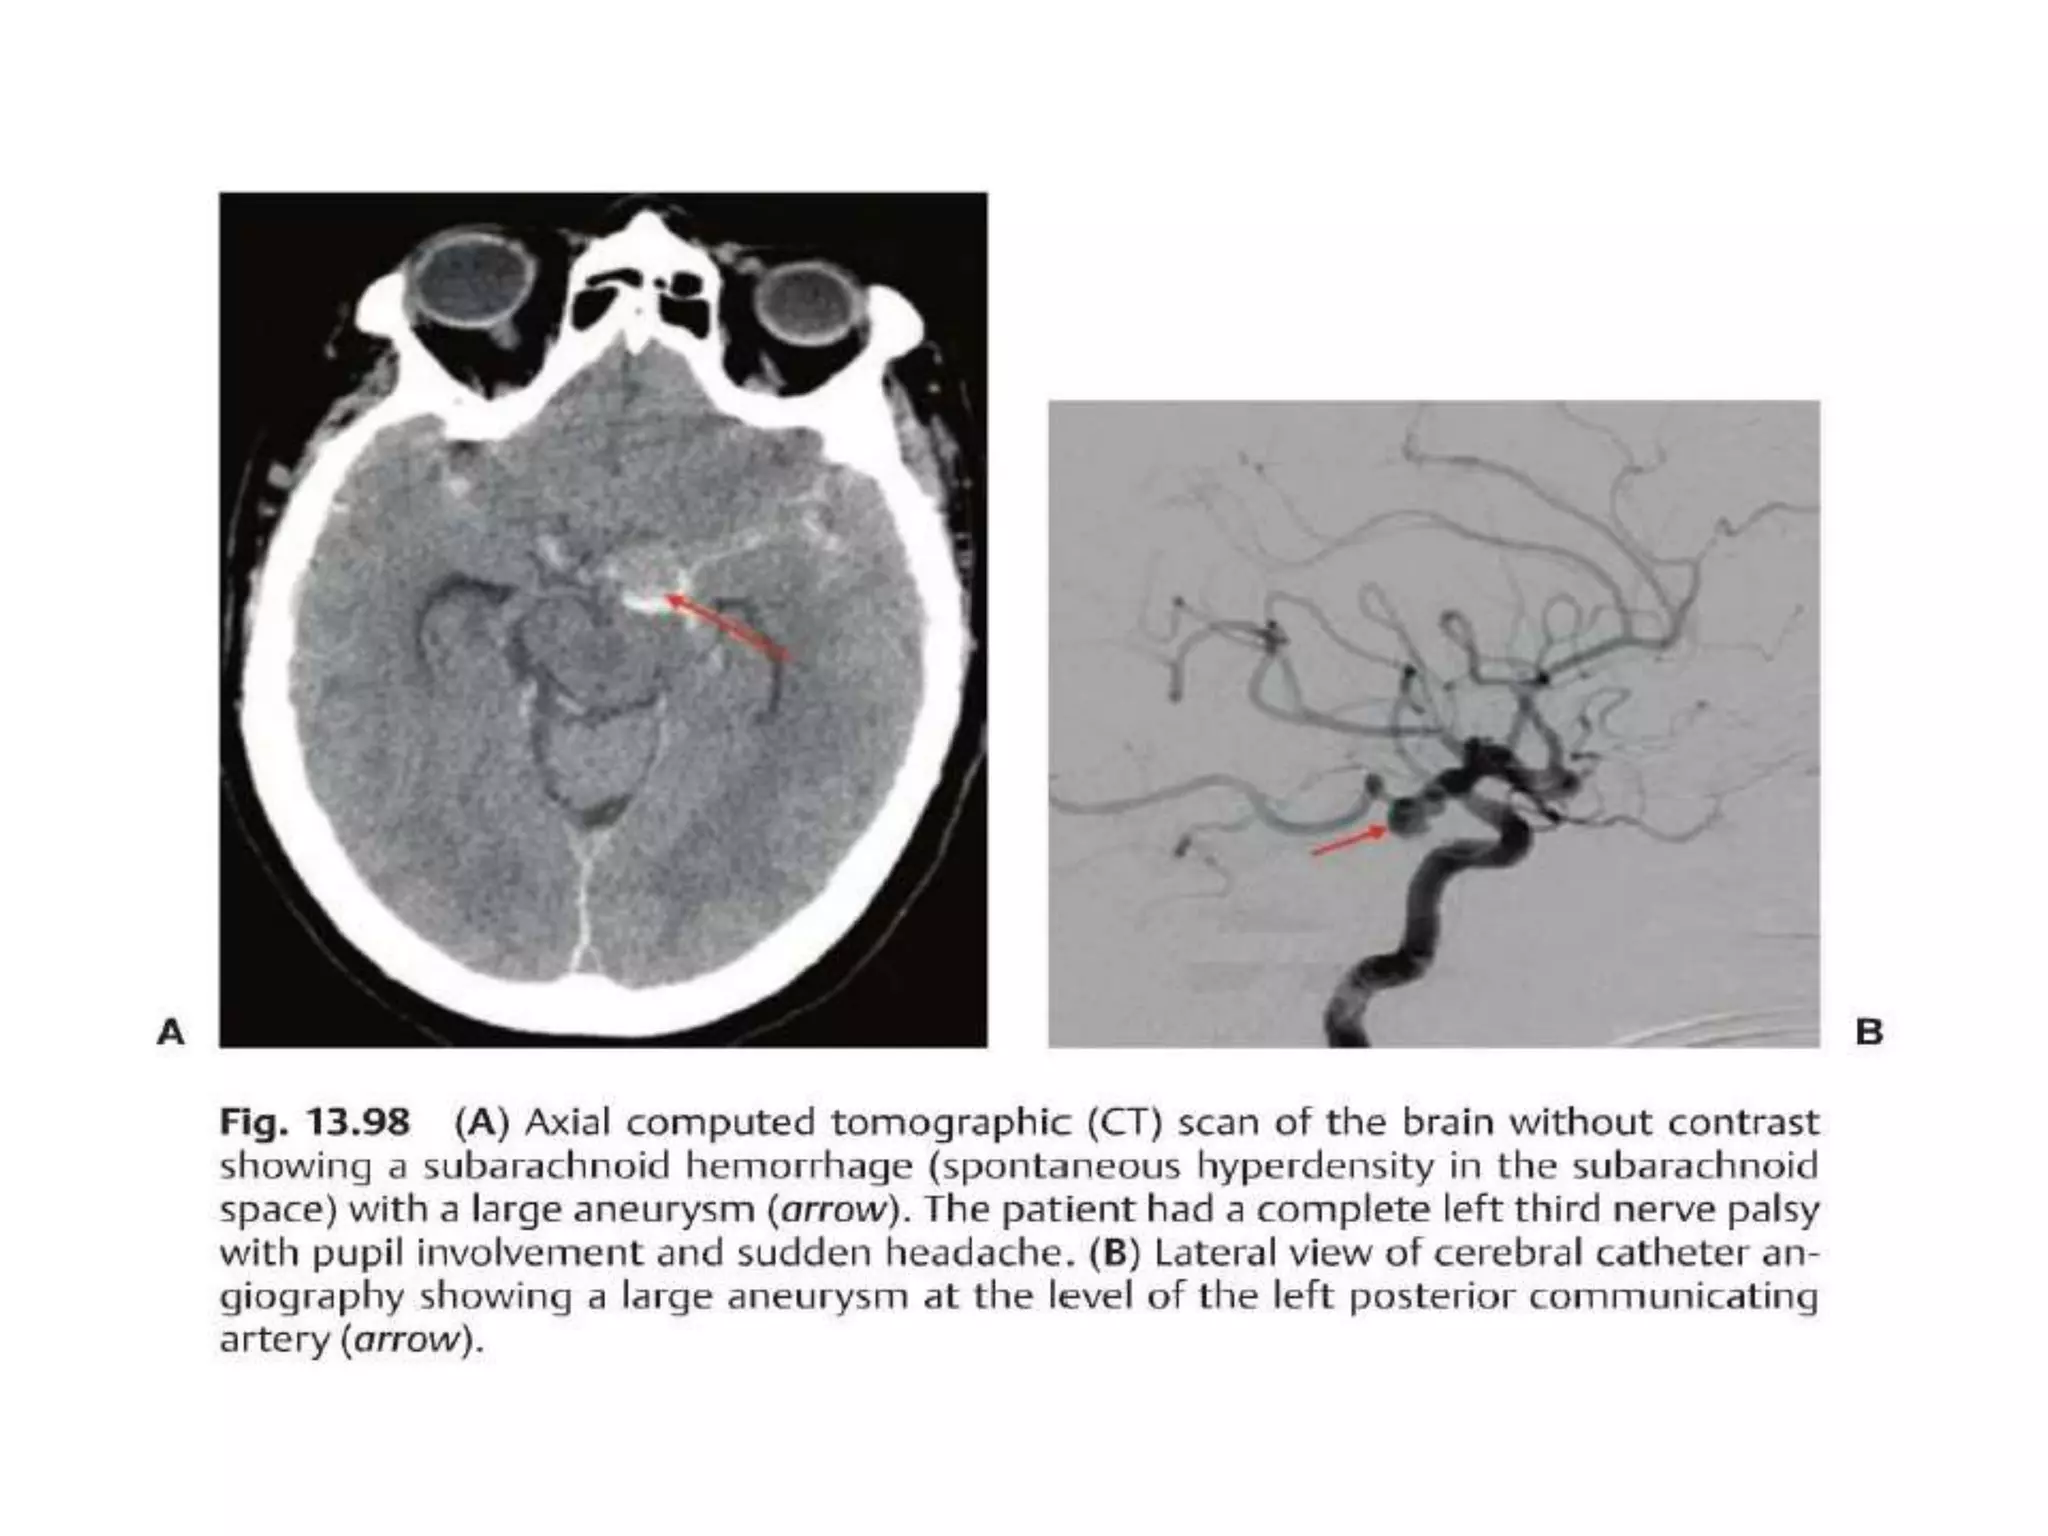

3rd n. anatomy

• Complex of subnuclei(dorsal of midbrain) –>subarachnoid space-

>sup. Cerebral a. and post. Cerebral a.-> cavernous sinus->sup.

orbital fissure, annulus of zinn->sup. division(levator, SR), inf.

Division(parasym,MR,IR,IO)

Classification

Pupil     muscle

Partial                  Not all muscle involved

Complete   Involvement                             Anisocoria

All muscle involved

Sparing                                 isocoria

3rd n. common cause

Evaluation

3rd n. anatomy •Complex of subnuclei(dorsal of midbrain) –>subarachnoid space- >sup. Cerebral a. and post. Cerebral a.-> cavernous sinus->sup. orbital fissure, annulus of zinn->sup. division(levator, SR), inf. Division(parasym,MR,IR,IO)

Classification Pupil muscle Partial Not all muscle involved Complete Involvement Anisocoria All muscle involved Sparing isocoria